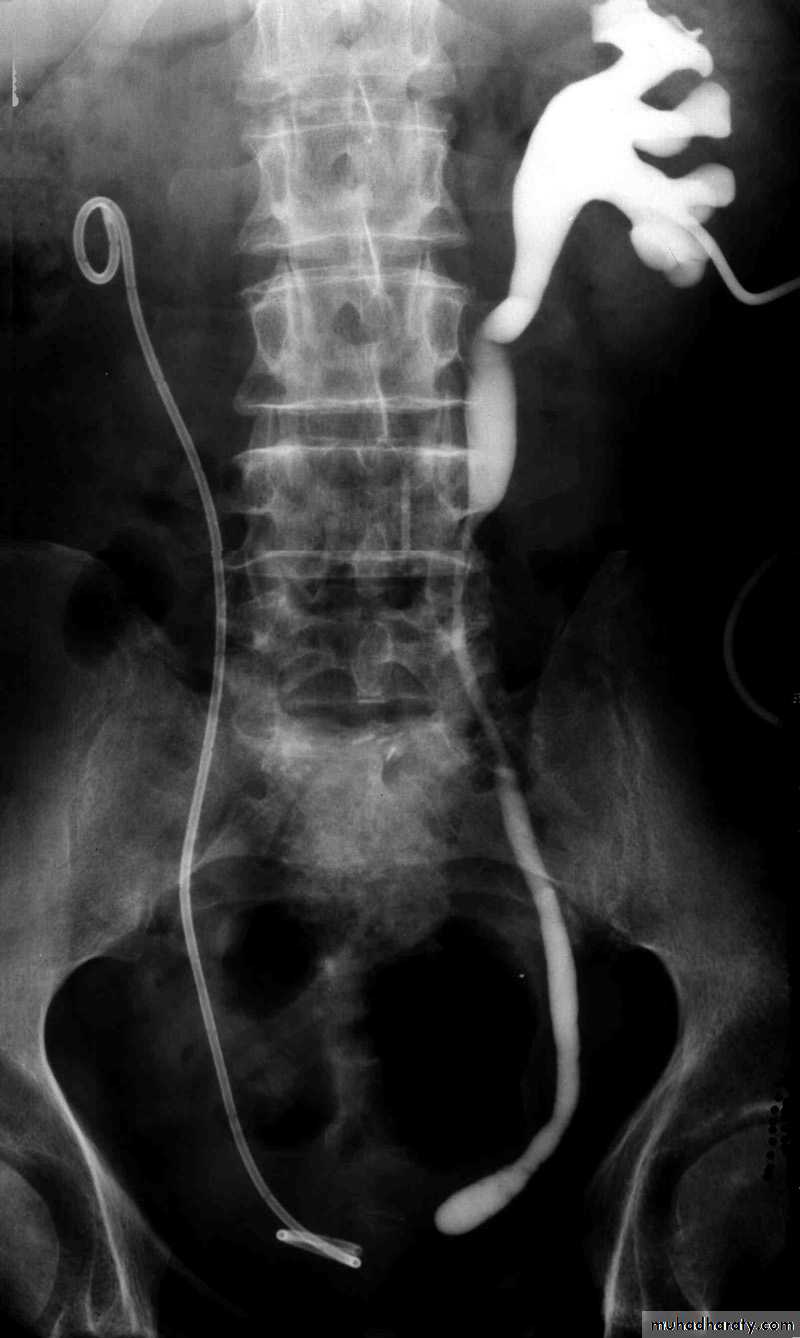

Postcaval (Retrocaval) ureter (Preureteral Vena Cava )

Urology

The right ureter pass behind the inferior vena cava

This might causes obstruction

Vascular abnormality

Incidence: about 1 in 1500

Although it is congenital, most patients present at 3rd or 4th decade.

Diagnosis: IVU

Treatment:

surgical correction involves ureteral division, with relocation and ureteroureteral or ureteropelvic reanastomosis,

usually with excision or bypass of the retrocaval segment, which can

be aperistaltic